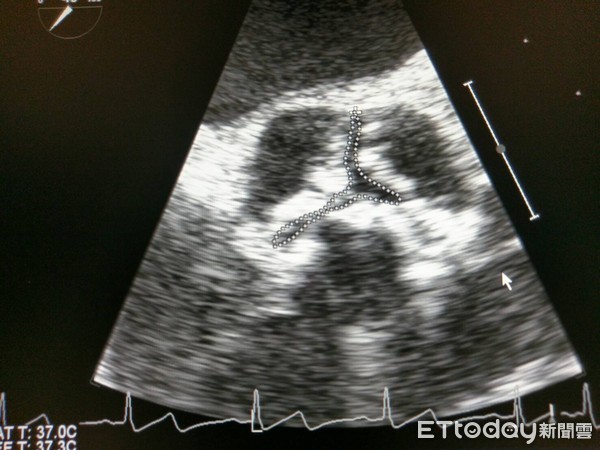

▲主動脈瓣膜狹窄好發於80歲以上老人。(圖/示意圖,非文中當事人/記者李毓康攝)

黃啟弘表示,主動脈瓣膜狹窄好發於80歲以上老人,主動脈瓣膜是三瓣,但亞洲人僅有二瓣比例比西方人高出甚多,而僅二瓣的民眾會提早於60-70歲發生主動脈瓣膜狹窄。